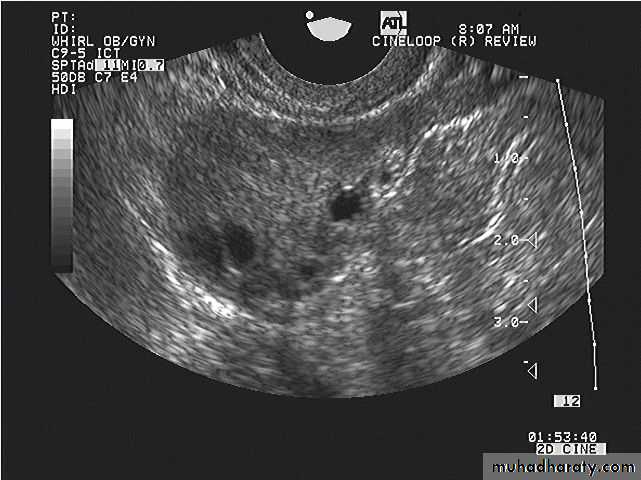

Ovarian hyperstimulation syndrome (OHSS):

This young adult female patient was examined to evaluate the uterus and ovaries. She was under treatment for infertility and was using gonadotropins. Ultrasound images of the ovaries show grossly enlarged ovaries with large cysts (measuring 2.6 to 3 cms.) in both ovaries. These ultrasound findings are diagnostic of OHSS or ovarian hyperstimulation syndrome.

• Ovarian hyperstimulation syndrome (OHSS):

The ultrasound image again show hyperstimulated ovaries. Both ovaries are grossly enlarged and cystic.